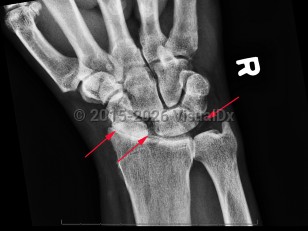

Imaging Studies image of Calcium pyrophosphate deposition disease - imageId=7889984. Click to open in gallery.  caption: '<span>CPPD of the wrist with  chondrocalcinosis of the TFCC and scapholunate ligaments. Note the  pronounced radiocarpal joint space narrowing at the radioscaphoid joint  with a stepladder appearance of the scaphoid to lunate transition which  is a finding compatible with CPPD arthropathy.</span>'

CPPD of the wrist with chondrocalcinosis of the TFCC and scapholunate ligaments. Note the pronounced radiocarpal joint space narrowing at the radioscaphoid joint with a stepladder appearance of the scaphoid to lunate transition which is a finding compatible with CPPD arthropathy.